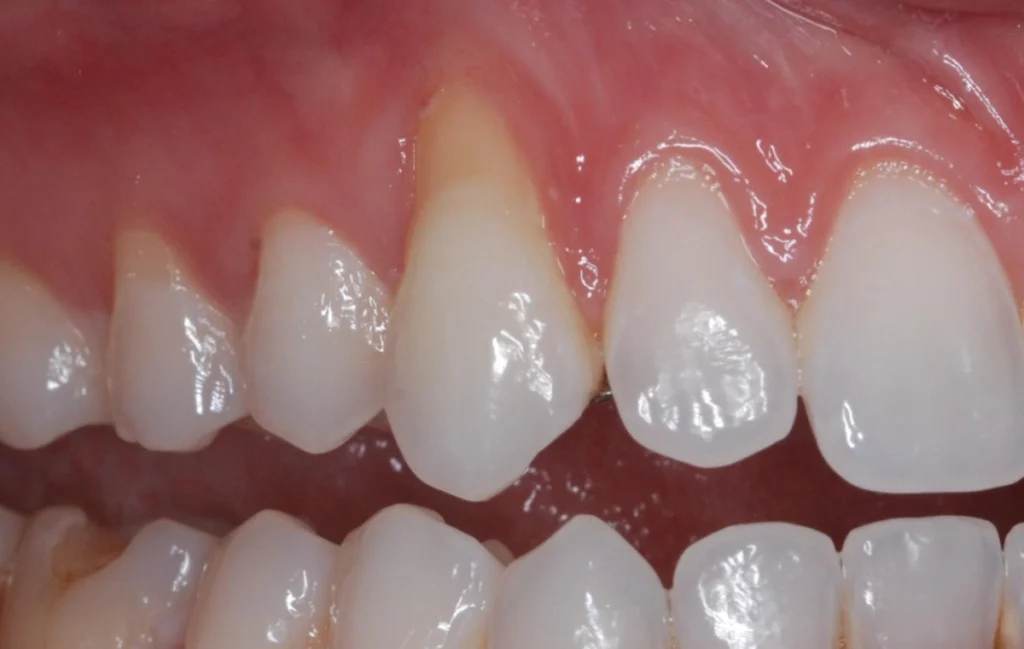

La récession gingivale

La récession gingivale est l’une des principales indications. Elle survient lorsque les gencives se rétractent, exposant les racines des dents. Cela peut être dû à un brossage agressif, à une maladie parodontale ou à un traumatisme. La chirurgie muco-gingivale couvre les racines exposées et renforce les gencives.